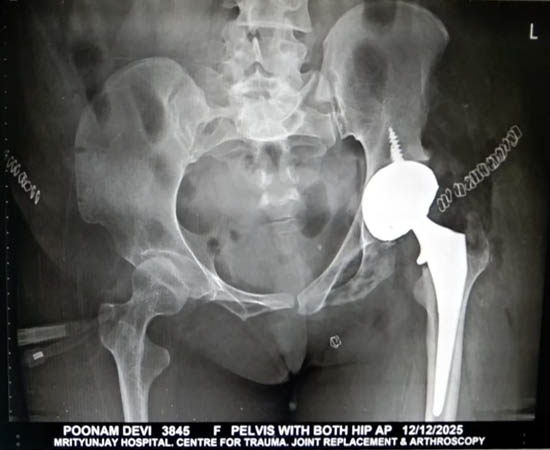

Post Operation for Bikini AMIS in a complex case

Post op Xray of Robotic DAA (Bikini AMIS)in a fused hip